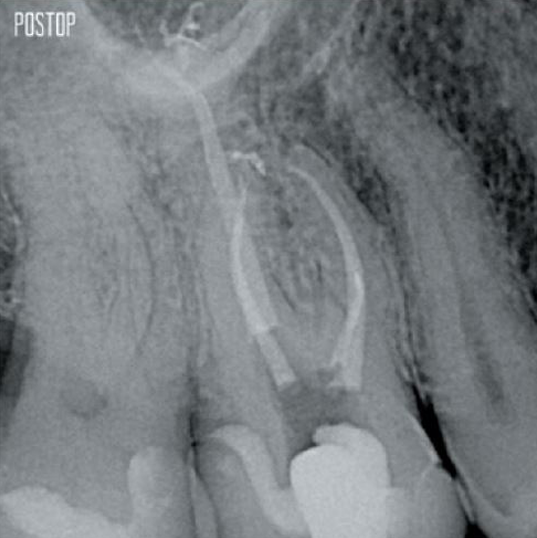

Fotos cortesia do Dr. Ahmed Salman

O tratamento bem-sucedido do canal radicular começa com o acesso adequado à câmara pulpar. O procedimento ideal fornece acesso aos orifícios do canal radicular com perda mínima de dentina.

Uma cavidade endodôntica conservadora (CEC) é recomendada com o sistema TruNatomy®.

A união da geometria da lima, as conicidades regressivas e o fio fino e altamente flexível permitem um tratamento eficiente do canal radicular, removendo a dentina apenas onde for clinicamente necessário.1

O TruNatomy® preserva o máximo de dentina possível1 e oferece uma solução completa, incluindo irrigação e obturação correspondentes.